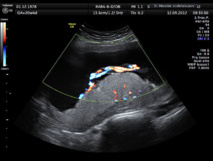

Harvey Kliman, científico investigador en el Departamento de Obstetricia, Ginecología y Ciencias Reproductivas de la Yale School of Medicine y autor principal del estudio; junto a sus colaboradores, descubrieron que ciertos pliegues anómalos de la placenta, así como un crecimiento celular anormal de esta (las llamadas inclusiones trofoblásticas) resultan marcadores clave para la identificación del riesgo de autismo en recién nacidos.

De este modo, se constató que las placentas de las familias del primer grupo presentaban un máximo de 15 inclusiones trofoblásticas, mientras que ninguna de las placentas del grupo de control tenía más de dos inclusiones trofoblásticas, informa la Universidad de Yale en un comunicado.

Kliman afirma que una placenta con cuatro o más inclusiones trofoblásticas puede predecir, con una probabilidad del 96,7%, el riesgo de autismo de un recién nacido.